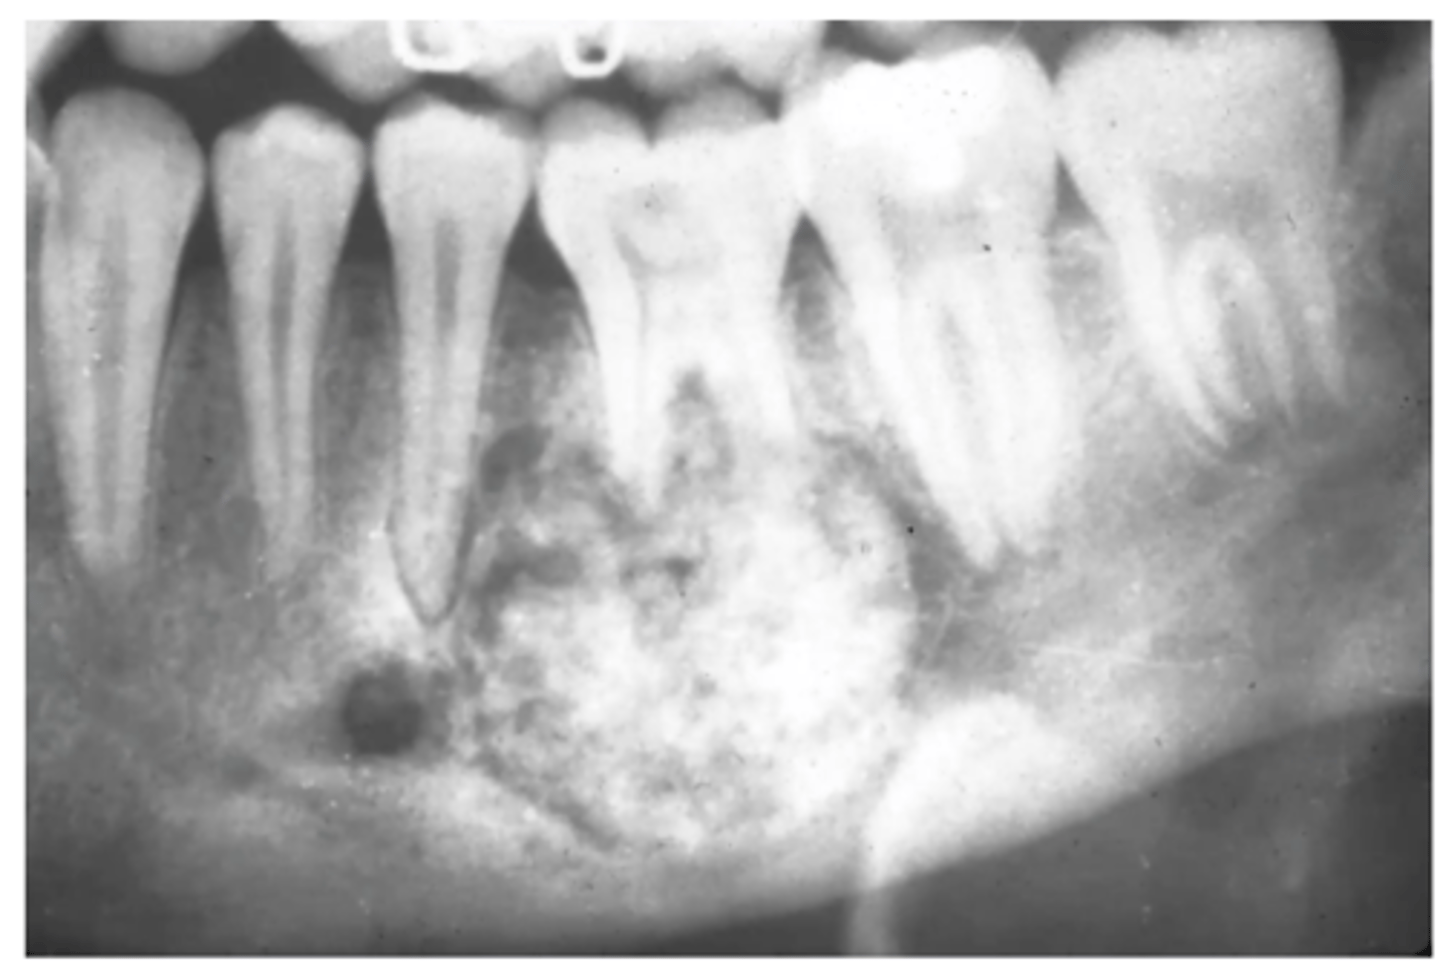

Diffuse sclerosing is seen in which condition?

Florid Osseous Dysplasia

What happens to the inferior border of the mandible in diffuse sclerosing?

Thinned